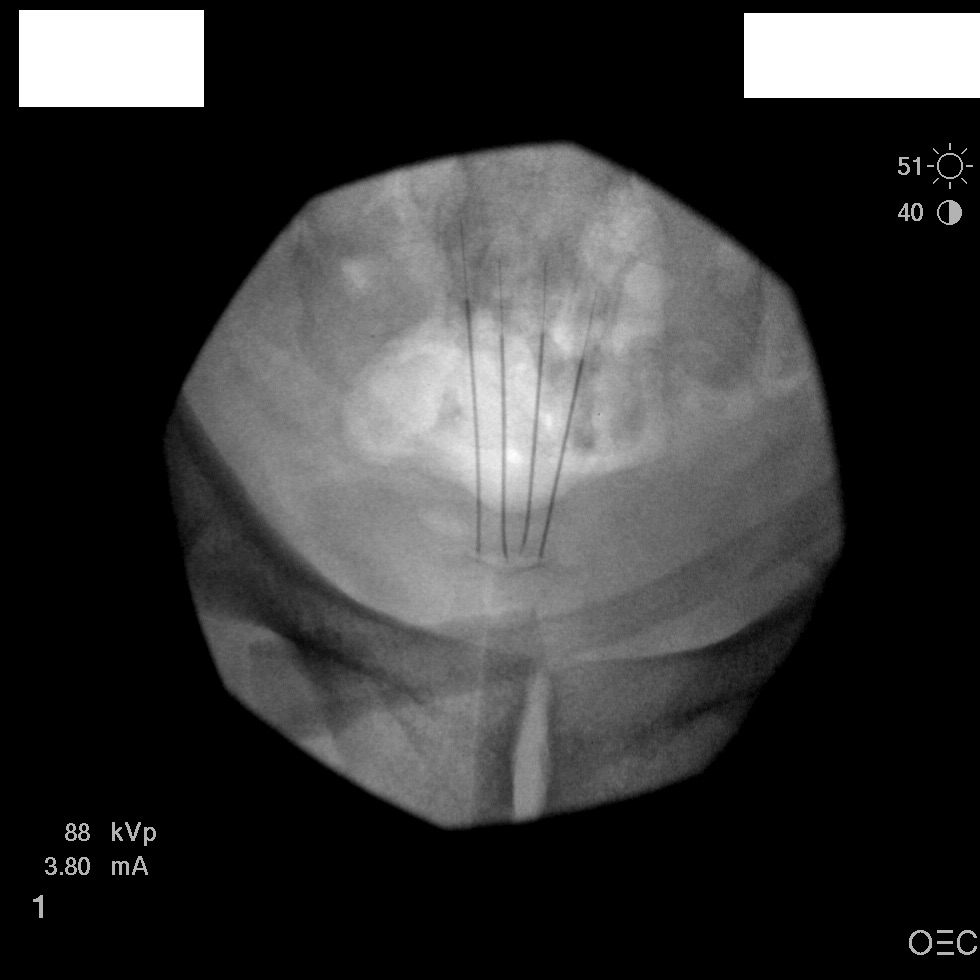

I have a patient with several months of coccyx pain. Worse with sitting, TTP over coccyx. Otherwise normal exam. No trauma, but she has an anteriorly displaced coccyx. Failed NSAIDs and no one around me does good pelvic floor PT. I scheduled her for ganglion impar injection, but her insurance won't pay for it. They wouldn't even let me to a peer-to-peer... they just straight up said they won't cover it. Any other treatment options? I don't want to send her to a surgeon. Thanks.